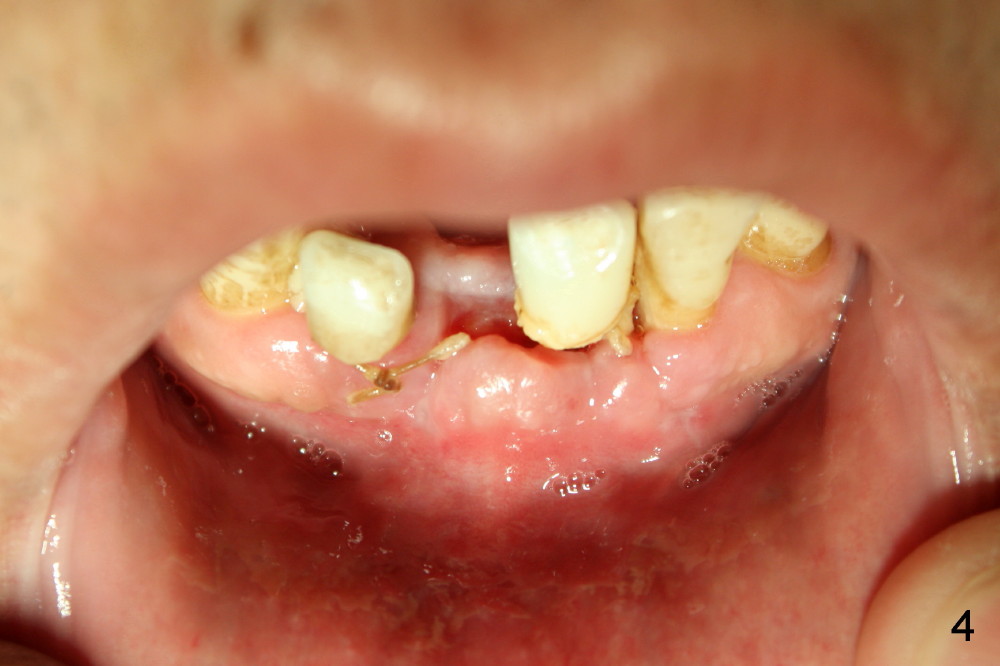

The mesial incision is found to dehiscence 7 days postop (Fig.3). Perio dressing dislodges one day postop. Perio dress is re-applied at follow up, but it is detached soon. Fortunately the wound shows sign of healing 14 days postop (Fig.4). The wound heals 5 weeks postop, although the top microthreads are exposed (Fig.5). In all, incision should be avoided as much as for immediate implants, anterior and posterior.